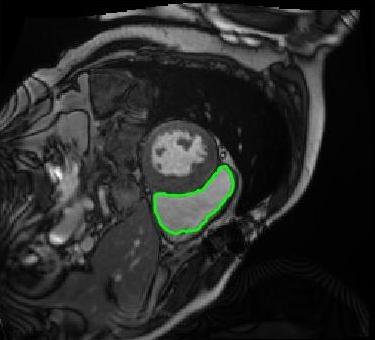

4.3 Comparison with cardic MR images for right ventricle segmentation

Cardiac MRI images often suffer from intensity inhomogeneity due to the varying magnetic susceptibility of cardiac tissues. This can lead to ambiguous boundaries, making it hard for models to consistently identify the left ventricle. Moreover, the heart is composed of several complex anatomical structures, including chambers, valves, and surrounding tissues. Accurately delineating the borders between these various components can be difficult, especially when they are closely positioned or exhibit similar intensity characteristics. In this section, we demonstrate the effectiveness of the RefLSM in segmenting cardiac MR images. The cardiac MR images are standardized to a size of . To enhance the credibility of the proposed model, we segmented 5 cardiac MR images compared the results with 6 other models, including the ALF [MA2019201], LoGRSF [DING2017224], ABC [WENG2021115633], RESLS[8765635], ICTM [WANG2022108794] and FeaACM [XUE2024110673] models. Fig. 5 displays the partial results from all the segmentation models. It is clear that the segmentation results from the RefLSM closely align with the ground truth of the left ventricle segmentation. However, the ALF model demonstrates relatively poor ability to capture the overall structure of the left ventricle; it exhibits limitations with precise boundary detection, particularly in areas of intensity inhomogeneity. Consequently, the evolution curve of the ALF fits into an unstable wave-like result. Suffering from intensity inhomogeneity and surrounding anatomical structures, the LoGRSF model, ABC model and RESLS model all represent over-segmentation and under-segmentation to some extent. Additionally, the results in the 6th column of Fig. 5 show multiple instances where where the ICTM model inaccurately identifies adjacent myocardial tissues as part of the left ventricle due to their similar intensity, leading to false positives. While the FeaACM demonstrates some ability to segment the left ventricle, it is not robust and fails to segment the 5th row of Fig. 5. The 2nd and 3rd rows also include small adjacent excessive regions. In contrast, our proposed model demonstrates marked improvements in accurately capturing the left ventricle’s boundaries. It effectively addresses challenges associated with severe intensity inhomogeneity and noise, resulting in better segmentations. The proposed method appear to maintain better structural integrity in the segmented images, closely aligning with the ground truth.

To quantitatively measure the segmentation results of each model, we compute the Dice and Precision values for left ventricle segmentation. Moreover, we opted for a voilin plot to effectively compare the RefLSM with six other models, as shown in Fig. 7. The results clearly demonstrate that the RefLSM yields superior Dice and Precision values than the other representative models, indicating its closer alignment with the ground truth and highest segmentation accuracy.